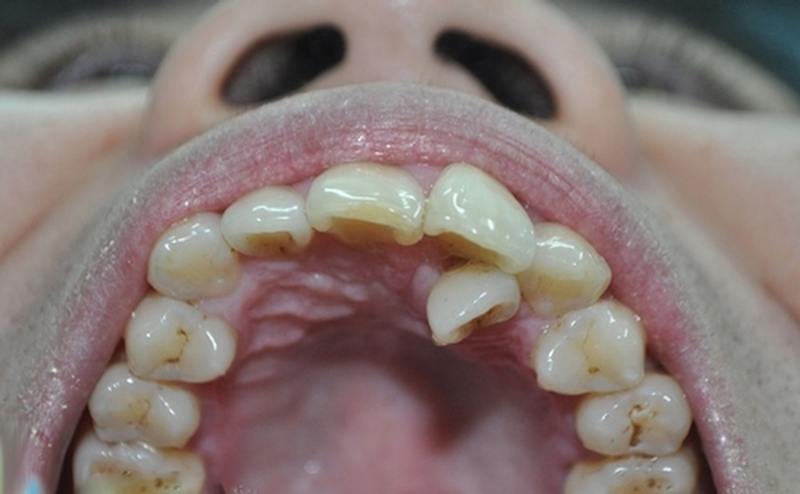

Không sờ thấy răng trong vùng xương ổ răng

Đây cũng là một trong những dấu hiệu răng mọc ngầm bạn cần chú ý. Bạn không sờ thấy răng trong miệng dọc theo vùng xương ổ răng. Hoặc có một vùng lợi xuất hiện trồi lên bất thường khi sờ vùng xương ổ răng.